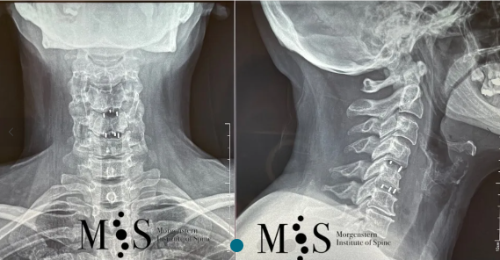

X-ray in A/P (left figure) and lateral (right figure) figures of a titanium

interbody cage placed at level C5/C6 with endoscopic surgery